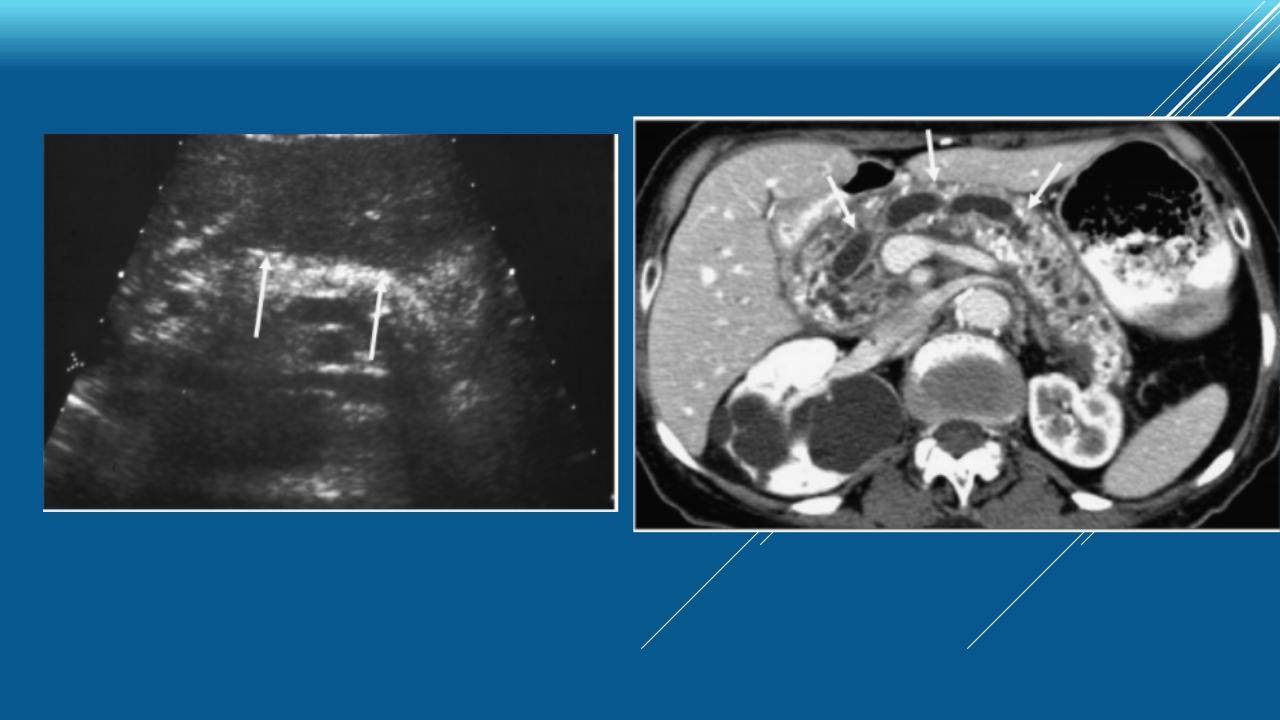

УЗ- и КТдиагностика хронического панкреатита

Хронический панкреатит: диагностика

Отсутствие изменений при условии полной визуализации железы

Наличие одного из перечисленных изменений:

Небольшая дилатация панкреатического протока (2-4 мм) в теле железы

Общее увеличение размера поджелудочной железы менее чем в 2 раза

Дополнительно – наличие одного из перечисленных изменений:

Дилатация панкреатического протока (>4 мм)

Нерегулярность контуров панкреатического протока

Наличие полости/полостей <10 мм

Гетерогенность структуры поджелудочной железы

Повышение эхогенности стенки протока

Неровные контуры головки или тела поджелудочной железы

Фокальный некроз или ↓ объема паренхимы

Наличие полости/полостей >10 мм

Внутрипротоковые дефекты наполнения

Наличие камней/кальцификации поджелудочной железы

Обструкция (стриктура) панкреатического протока

Выраженная дилатация или неровность контуров панкреатического протока

Поражение соседних органов